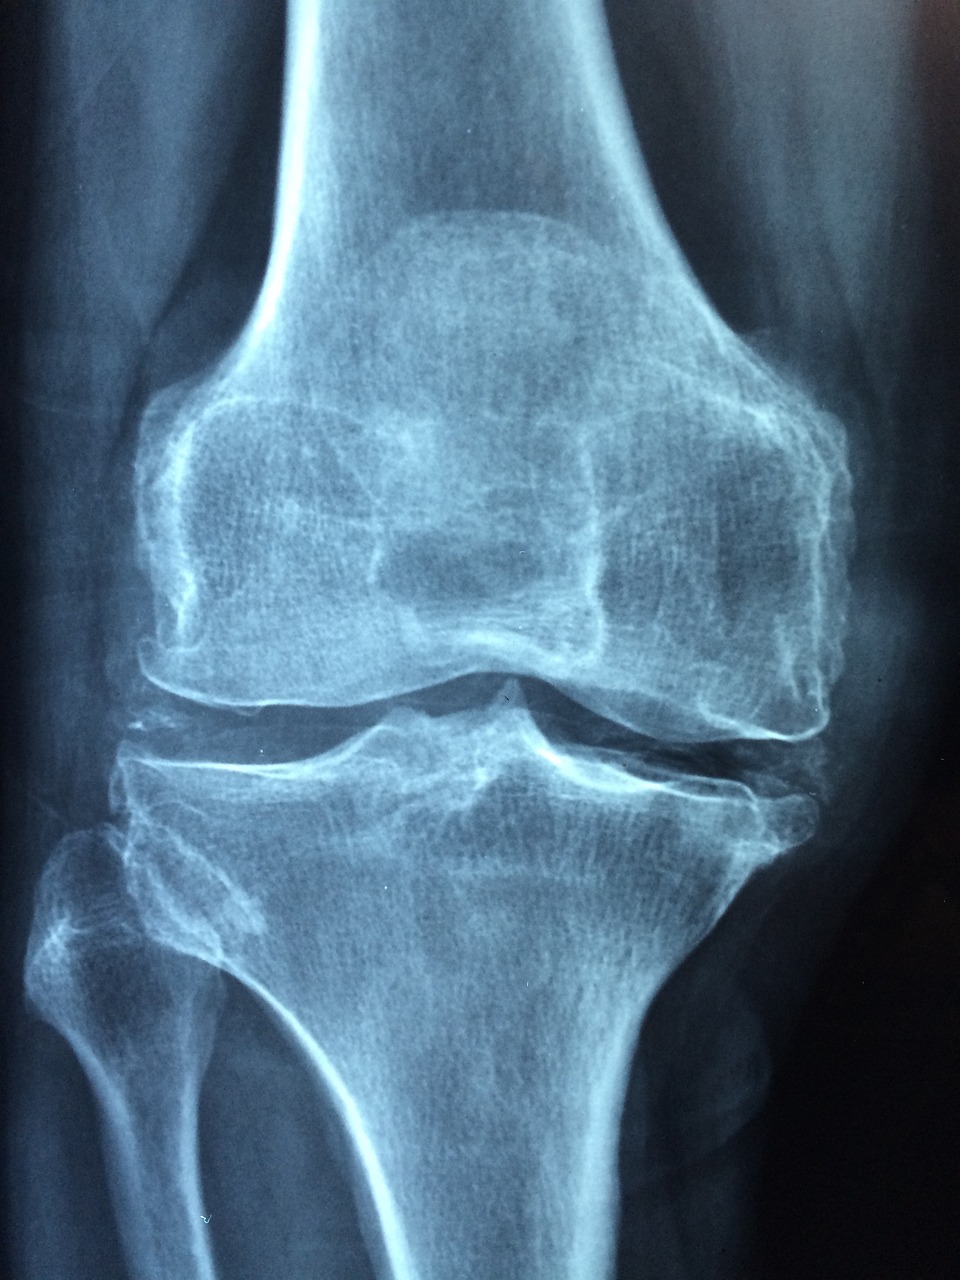

무릎 인공관절 수술 후 스타킹 착용은 단순한 회복 보조 도구가 아닙니다. 특히 수술 직후에는 혈액 순환이 느려지면서 혈전이 생길 수 있는데, 이때 압박스타킹은 다리의 정맥 혈류를 도와 혈전 생성을 막는 중요한 역할을 합니다.